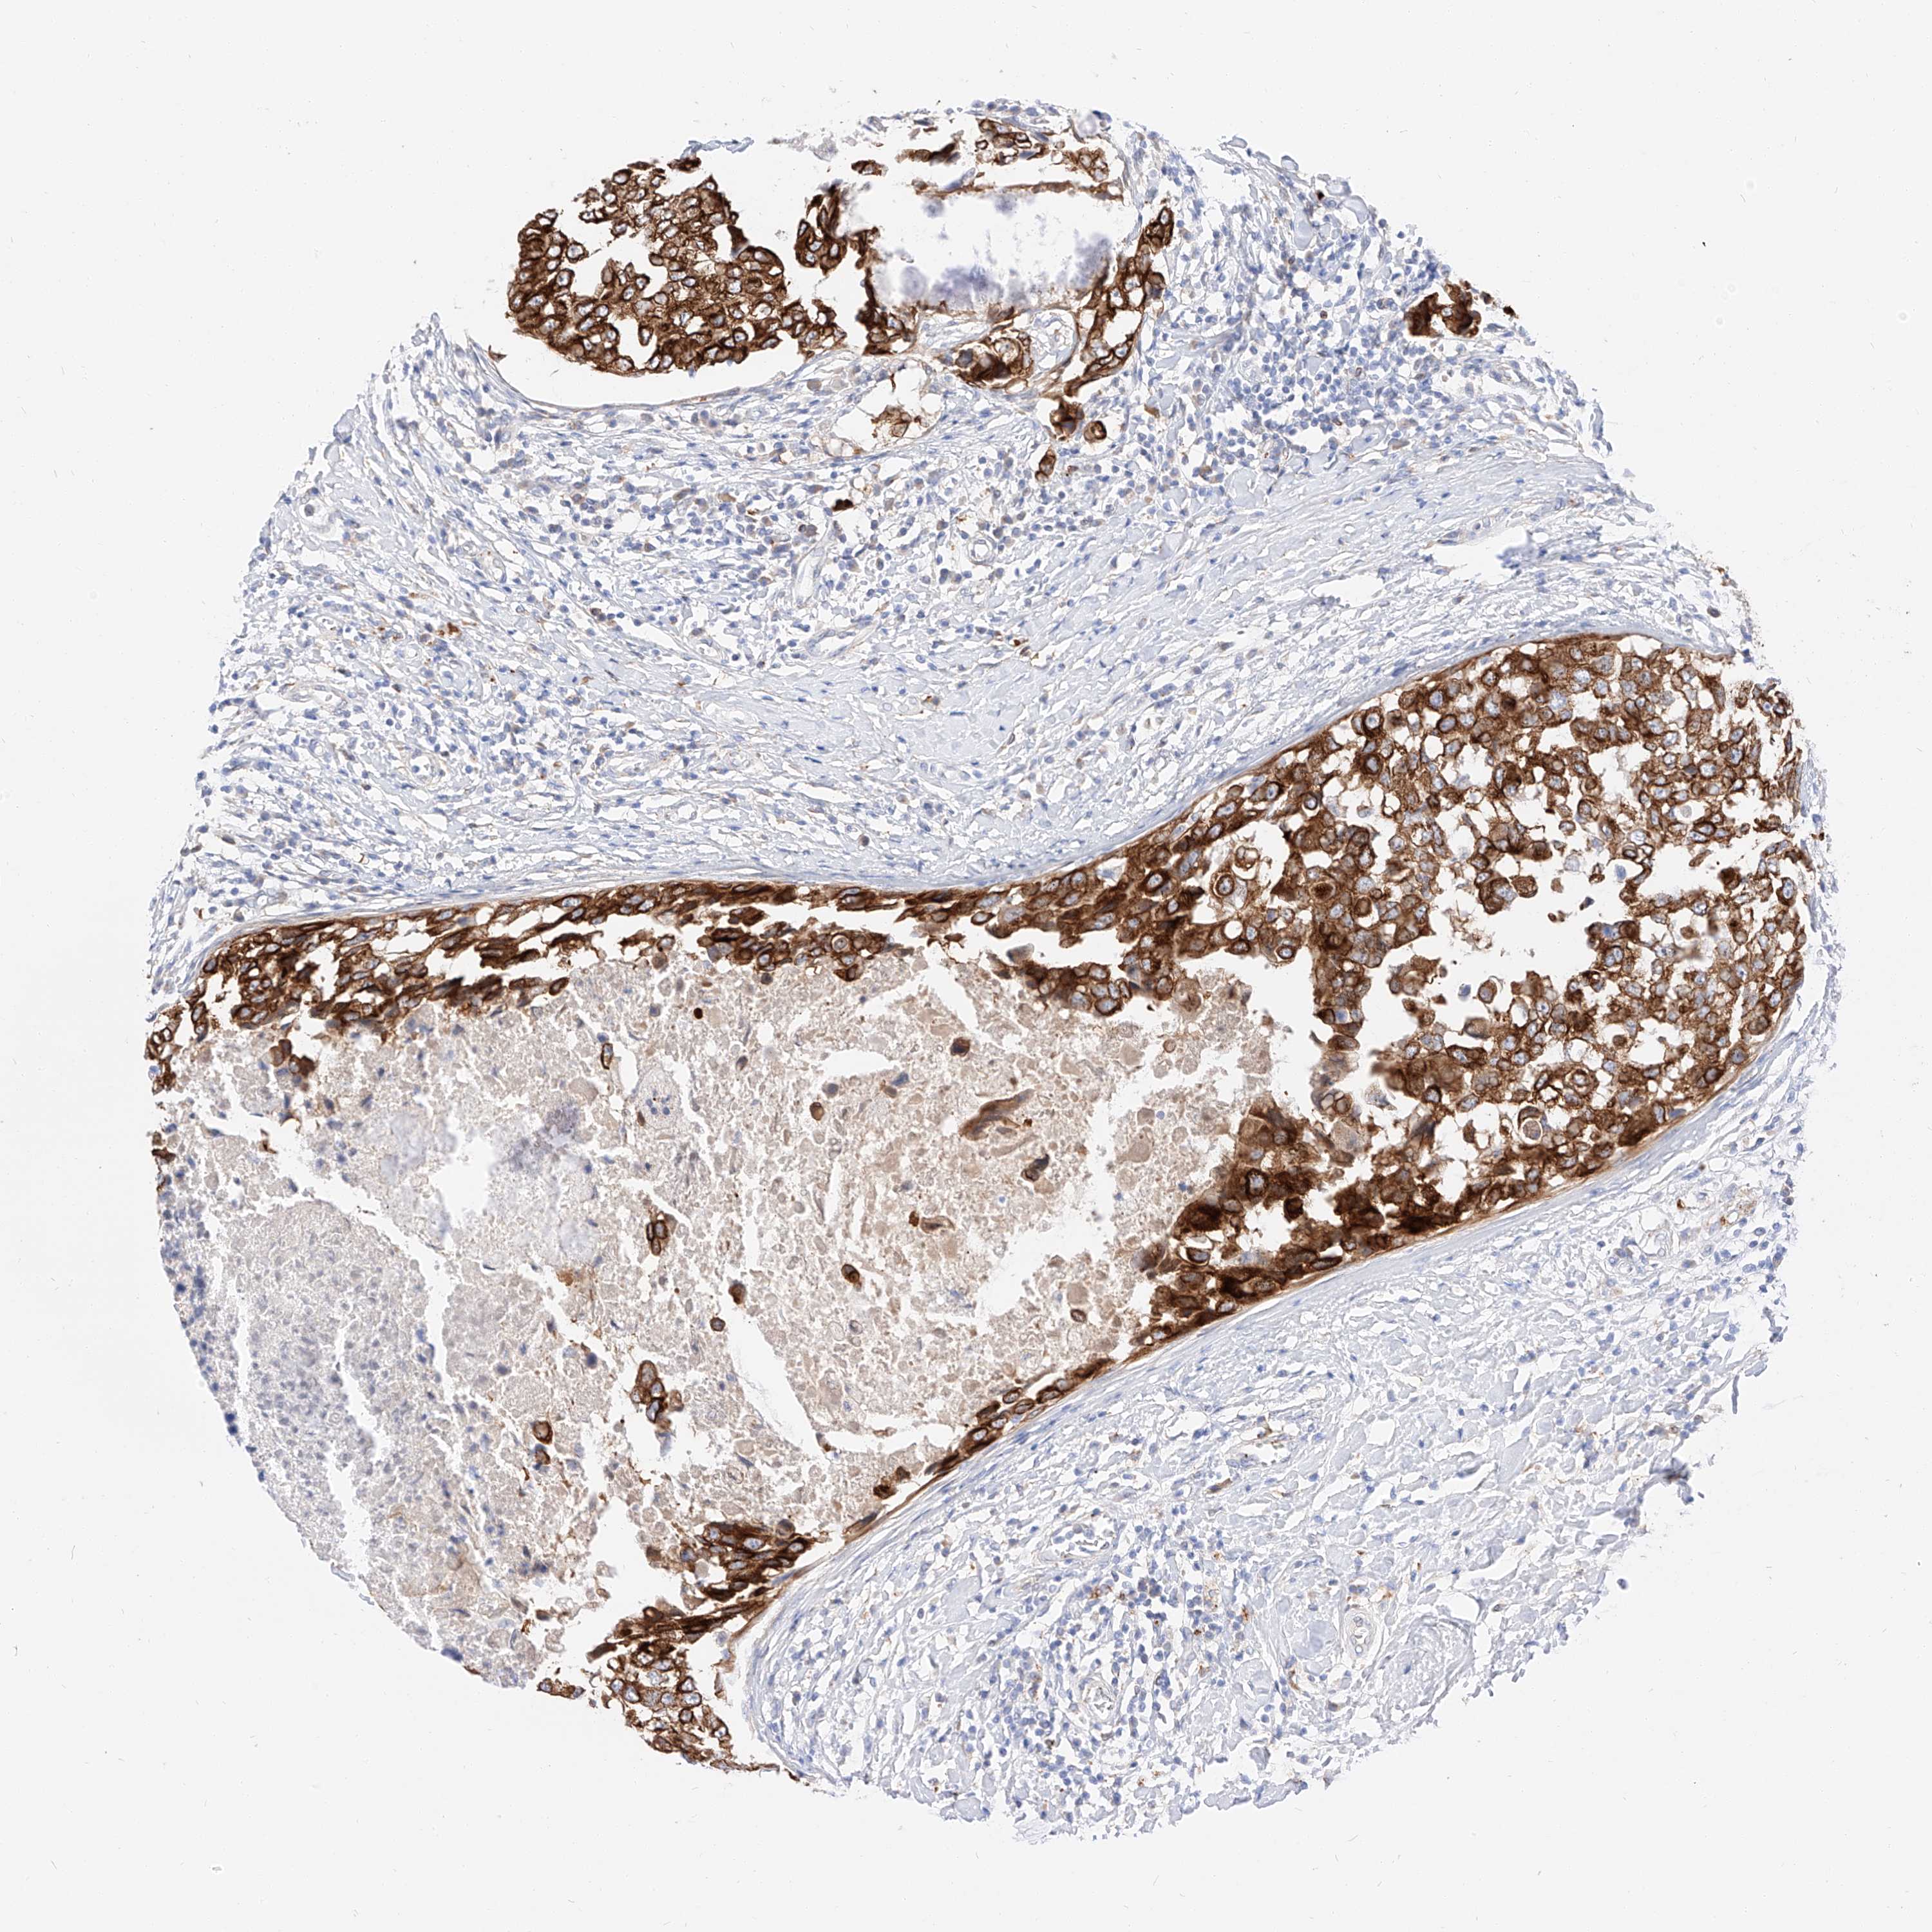

CANCER BREAST CANCER Show tissue menu

BRCA TCGA BRCA VALIDATION PROTEIN EXPRESSION